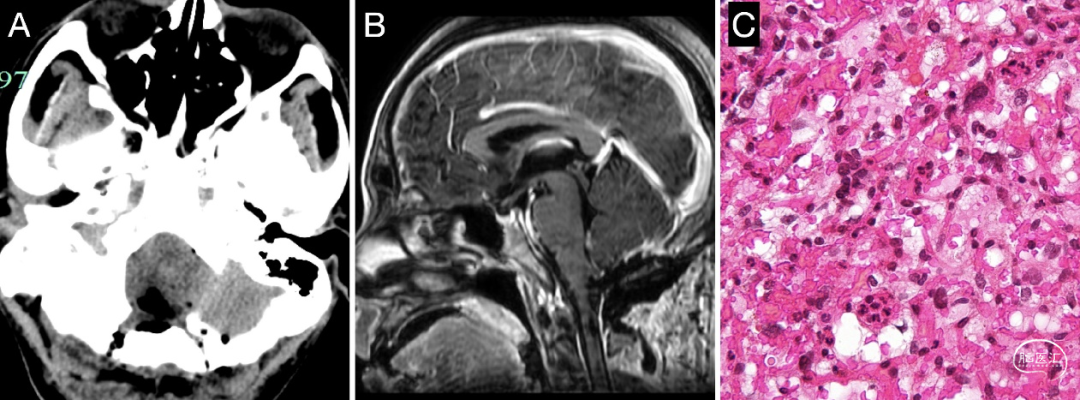

入院后完善相关检查,颅脑MR增强提示颈髓背侧17×15×23mm团状信号,T1等信号,T2不均匀高信号,T2 FLAIR呈稍高信号,增强扫描后病灶呈显著强化,继发脊髓空洞形成(图1 A-C)。进一步头颅CTA提示肿瘤为富血管病变,大部分由右侧小脑后下动脉供血,小部分由右侧椎动脉供血(图1 D- E)。腹部B超未见明显肝、肾囊肿。眼底检查无明显异常。术前诊断:延髓血管母细胞瘤(实体型)。入院评估无手术禁忌,2018年10月18日行开颅肿瘤切除术。

图1. 术前颅脑MR增强及CTA。头颅MR增强提示肿瘤位于枕骨大孔区,延髓被向前推挤明显,肿瘤强化明显(实线箭头),伴有颈段脊髓空洞改变(虚线箭头)(A-C)。CTA提示肿瘤为富血供病变,供血动脉为PICA来源,伴有粗大的引流静脉(D- F)。